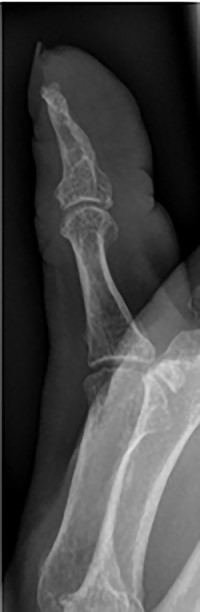

Her blood tests on presentation were unremarkable and X-rays of her right thumb showed a lytic lesion involving the tuft of the distal phalanx (Figs. 4 and 5). She was admitted to the hospital and was treated as having an infection of her right thumb with elevation and intravenous antibiotics. She underwent emergency surgery the next day for a washout and debridement of the right thumb. During the debridement in theatre, there was no pus in the pulp, but the bone was found to be eroded and soft, thus multiple specimens from the bone were sent for microscopy, culture and sensitivity, acid-fast bacilli (AFB) and histopathology.

Lateral X-ray of right thumb showing erosion of tip of distal phalanx and soft tissue swelling.